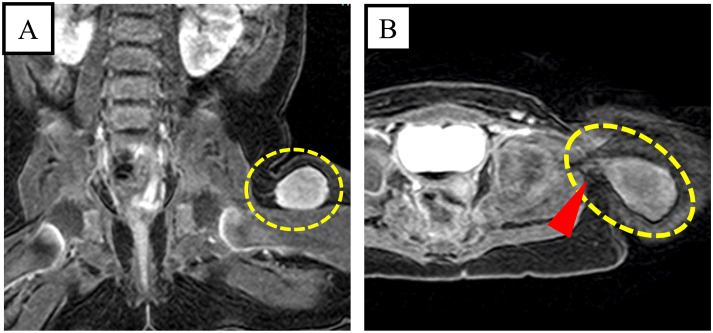

幼年黄疽瘤(JXG)是一种罕见的良性非朗格汉斯细胞组织细胞增生症,通常发生在新生儿和幼儿的头部、颈部或躯干上部的皮肤病变中。侵入肌肉组织的肌内 JXG 仅占所有 JXG 的 0.6%,而且大多发生在四肢或躯干的骨骼肌中。一名 5 个月大的女孩被转诊到我院。3 个月大时,她发现左大腿上有一个缓慢生长的肿块。磁共振成像(MRI)显示,她的左大腿上有一个 22 × 19 × 18 毫米的椭圆形肿块。首先,针刺活检结果提示为深部 JXG 或髓样肉瘤。因此,对其进行了边缘切除术。术中,肿瘤与左侧张肌筋膜粘连,一并切除。组织病理学检查显示,单核组织细胞样细胞呈弥漫性单层片状增生,胞浆苍白、嗜酸性、泡沫状,背景为肌肉和脂肪组织。细胞有丝分裂极少,无核不典型性或多核巨细胞。免疫组化分析显示,CD68(KP-1)和 CD163 阳性;溶菌酶弱阳性;CD1a、S100、髓过氧化物酶和 CD34 阴性。骨髓中未观察到胚芽增殖。患者被诊断为深部 JXG,并被安排进行定期体检和磁共振成像检查。尽管肿瘤边缘呈阳性,但患者在肿瘤切除 48 个月后情况良好,未出现局部复发。了解深部 JXG 的独特病理和详细的组织学评估对决策非常重要。

Juvenile xanthogranuloma (JXG) is a rare benign non-Langerhans cell histiocytosis that usually occurs in cutaneous lesions on the head, neck, or upper trunk of neonates and young children. Intramuscular JXG, which invades muscle tissue, accounts for only 0.6% of all JXGs and mostly occurs in the skeletal muscles of the extremities or trunk. A 5-month-old girl was referred to our hospital. At the age of 3 months, she presented with a slow-growing lump on her left thigh. Magnetic resonance imaging (MRI) showed a 22 × 19 × 18 mm oval mass in her left thigh. First, needle biopsy results suggested deep JXG or myeloid sarcoma. Therefore, marginal resection was performed. Intraoperatively, the tumor adhered to the left tensor fasciae latae muscle and was resected together. Histopathological examination revealed a diffuse monotonous sheet-like proliferation of mononuclear histiocyte-like cells with pale, eosinophilic, foamy cytoplasm with a background of muscle and fatty tissue. Minimal mitotic figures and no nuclear atypia or multinucleated giant cells were observed. Immunohistochemical analysis was positive for CD68 (KP-1) and CD163; weakly positive for lysozyme; and negative for CD1a, S100, myeloperoxidase, and CD34. No blast proliferation was observed in the bone marrow. The patient was diagnosed with deep JXG and scheduled for periodic physical examination and MRI. Despite positive margins, the patient fared well without local recurrence 48 months after tumor removal. Understanding the unique pathology of deep JXG and detailed histological evaluation are important for decision-making.